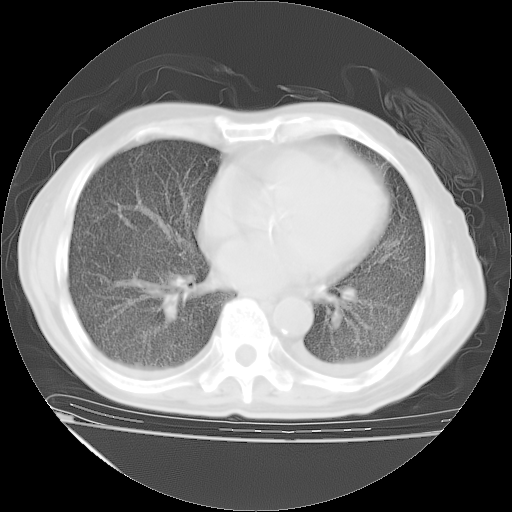

甲强龙80mg/日+抗结核治疗(异烟肼+利福霉素+乙胺丁醇)10天。复查肺部CT。

治疗10天肺部CT